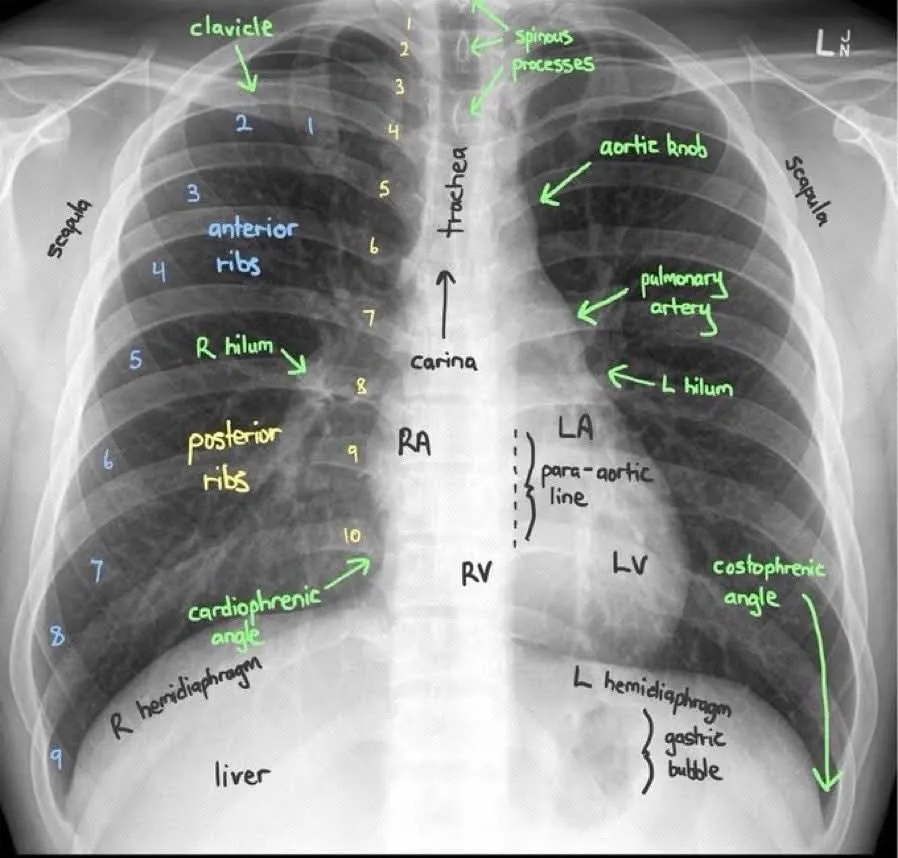

Chest X-Ray